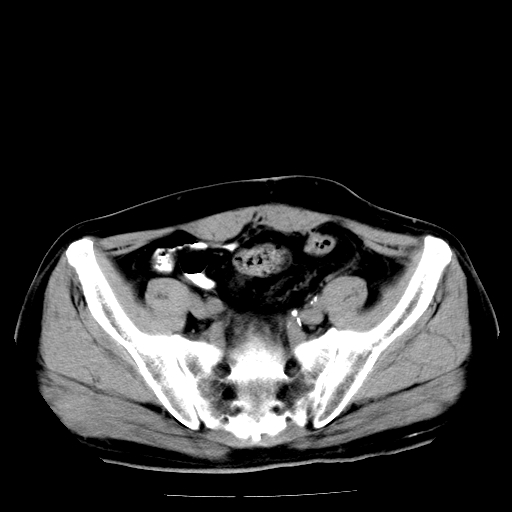

男,66岁,直肠癌术后一个月,化疗前ct检查。

直肠癌造瘘术后改变,周围淋巴结转移

前列腺肥大

直肠癌造瘘术后改变,盆腔多发淋巴结转移

直肠癌造瘘术后改变,直肠周围软组织增厚,盆腔多发淋巴结转移。前列腺肥大。